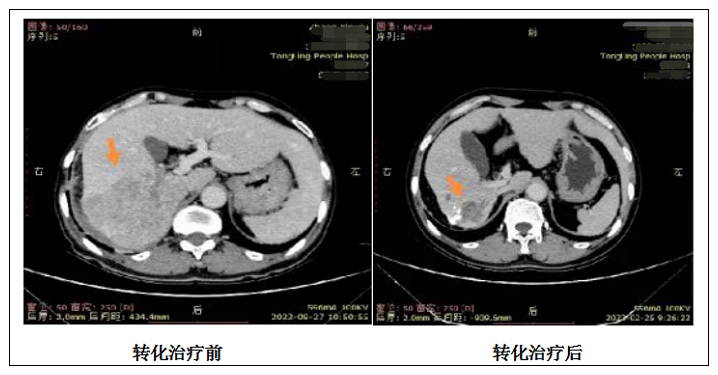

普外肝胆病区主任侯亚峰带领医疗团队进行多学科讨论后,决定采用“转化治疗”方案,即“肝癌介入+靶向药物+PD-1免疫治疗”多模式高强度全身治疗,待肿瘤缩小、降期后再行肿瘤切除术。经过肝癌介入治疗和“免疫治疗+口服靶向药物治疗”后,患者肿瘤有所缩小,转化治疗效果显著,有手术切除指征。侯亚峰团队为患者成功施行根治性肝癌切除术,术后病理提示肿瘤坏死,切缘阴性,达到根治性治疗。